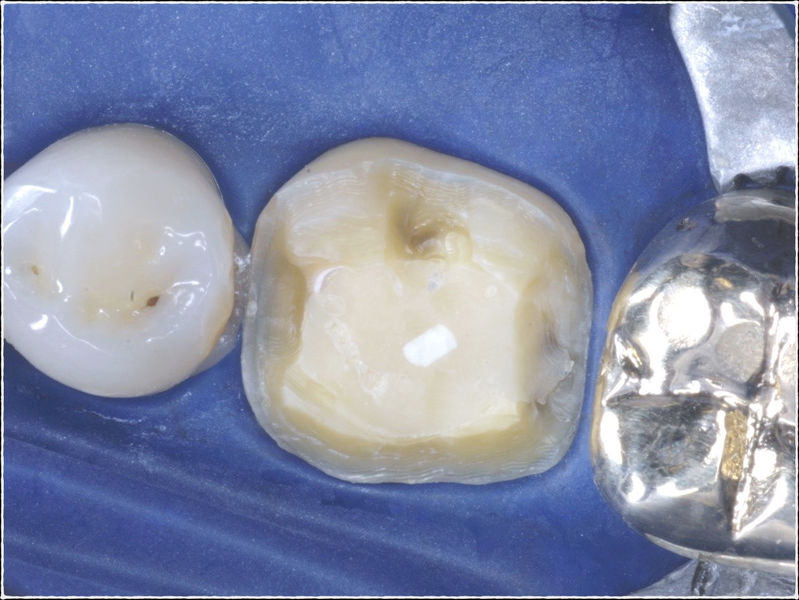

Restauraciones fabricadas en el laboratorio con materiales estéticos, los cuales cubren de manera parcial dientes posteriores. Se utilizan primariamente para restaurar dientes con caries, fracturas y/o defectos amplios. Para poder enviar el caso al laboratorio se toman impresiones utilizando materiales de impresión o técnicas modernas digitales.